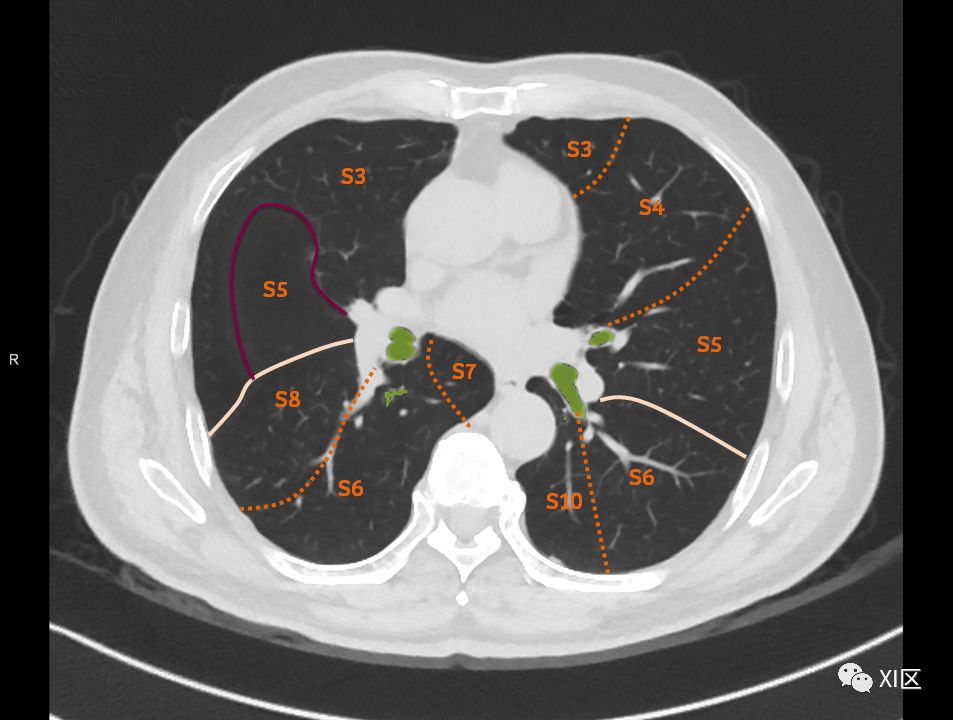

肺的断层分段示意图

在进行肺的分段时,可以上下观察浏览,沿着相应气管的走形可以更容易准确地进行分段。